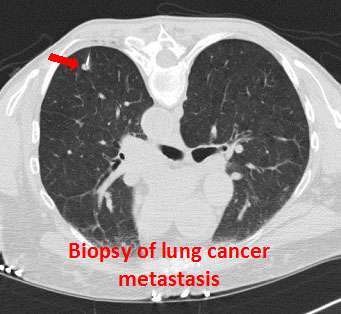

Diagnosis and Screenings

- Chest x-ray

- CT scan

- Sputum cytology

- Biopsy of the lung

- Bronchoscopy

- Thoracoscopy

- Thoracentesis

- Light and electron microscopy

- Immunohistochemistry